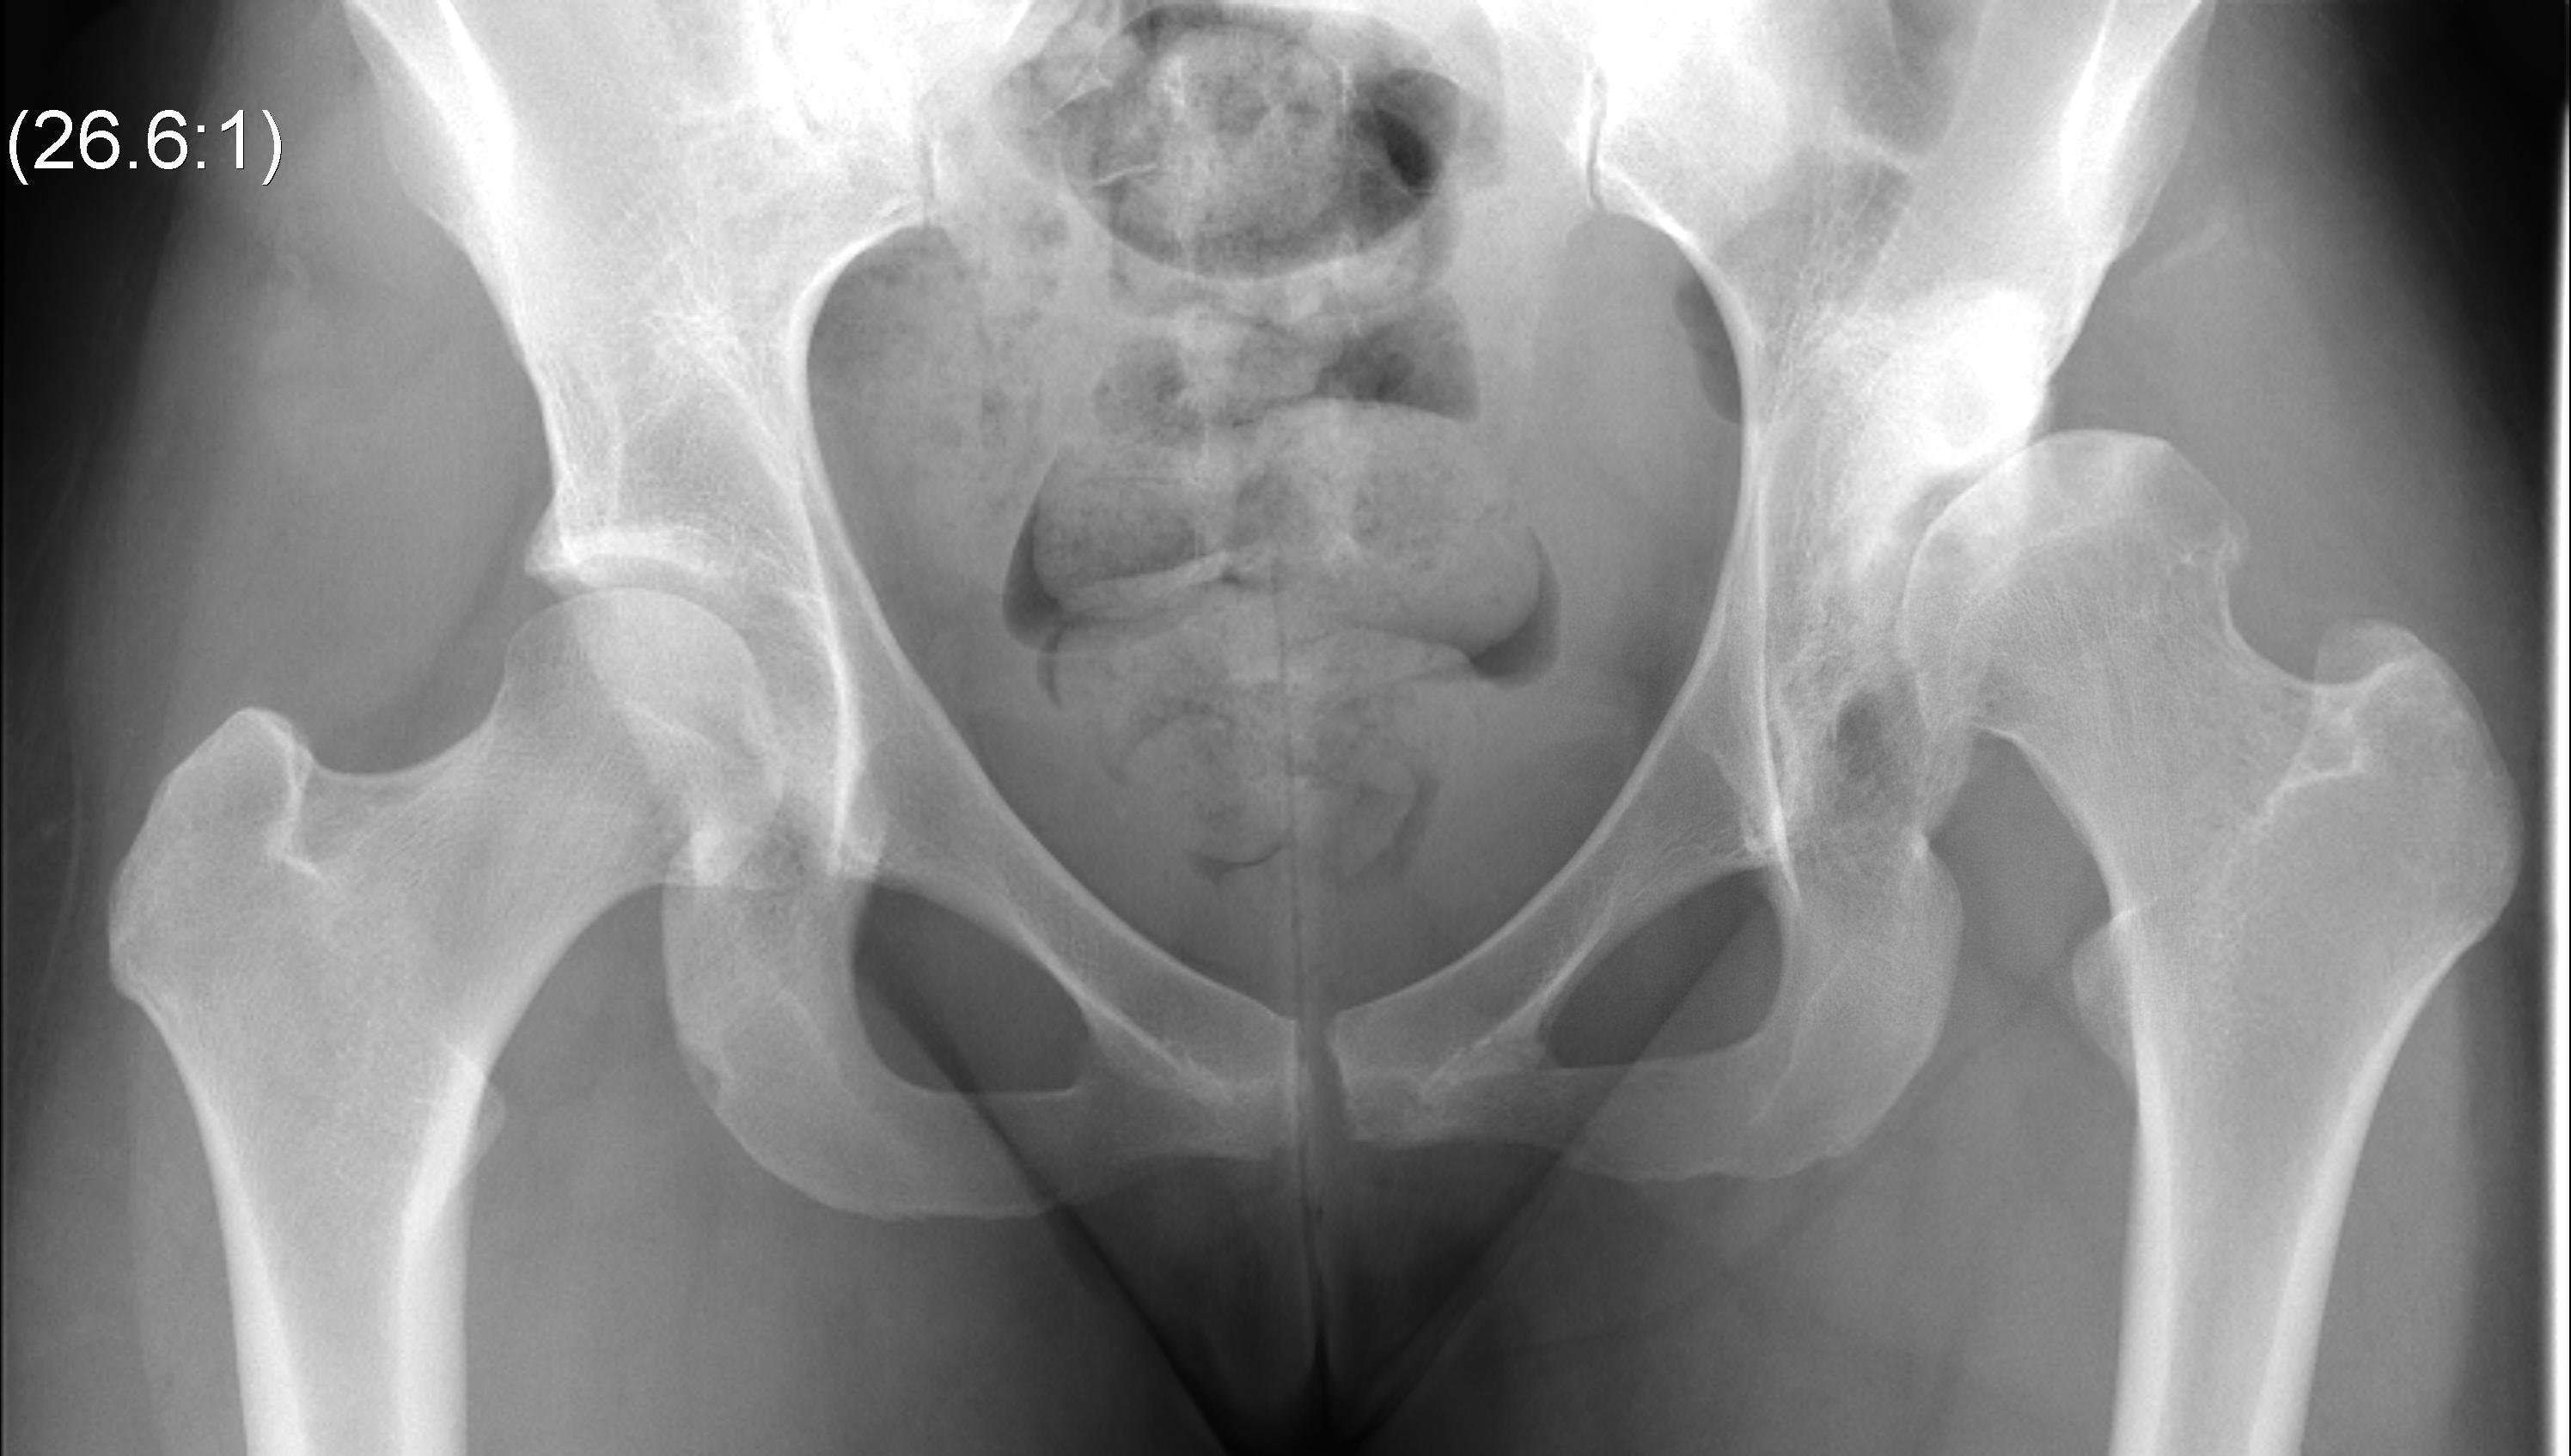

Crowe Classification

| Crowe Type | Definition |

|---|---|

| I | Subluxation < 50% vertical diameter femoral head |

| II | Subluxation 50 - 75% vertical diameter femoral head |

| III | Subluxation 75 - 100% vertical diameter femoral head |

| IV | Proximal migration of > 100% vertical diameter femoral head |

Crowe I

Crowe II

Crowe III

Crowe IV